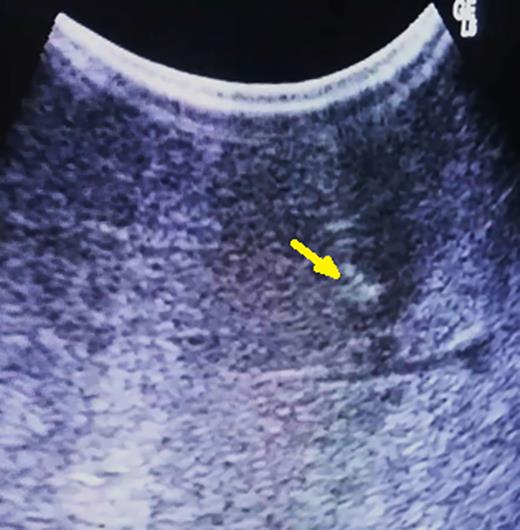

Based on preoperative image studies, the portion on the liver that contains the tumor is fully mobilized by transection of hepatic ligaments. Then, intraoperative ultrasonography is performed in order to achieve precise localization of the lesion and estimation of its deepness (Fig. 1).

Hypoechoic 5-mm lesion at 2 cm depth (metachronous metastatic tumor from colorectal carcinoma) (arrow).